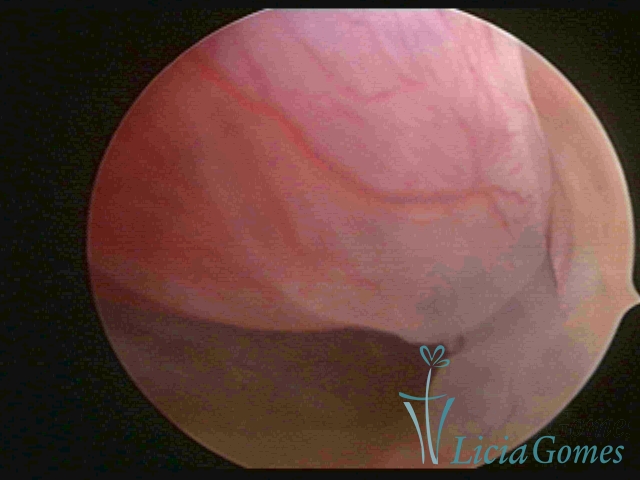

ENDOCERVICAL POLYPS

Benign tumors resulting from the reactive focal proliferation to inflammatory processes or hyperestrogenism situations, which may be sessile (with a large implantation) or stalked.